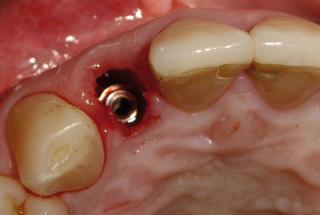

Clinical cases

MPI closely monitors clinical cases in the market to ensure their correct functioning and successful outcome.